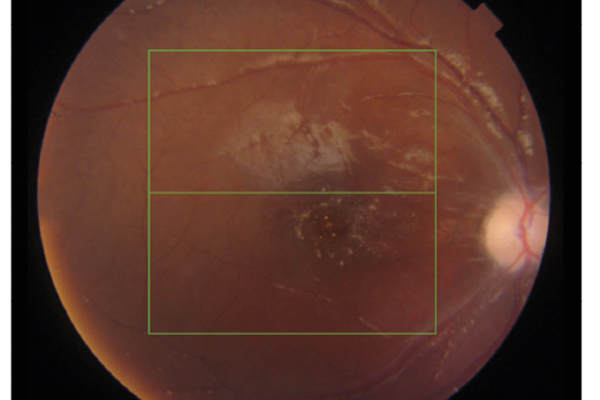

A paediatric case of central retinal artery occlusion following antibiotics and decompression surgery for orbital cellulitis